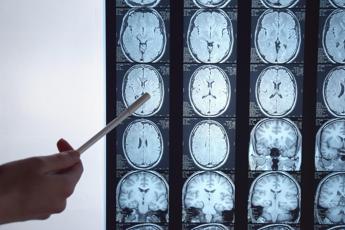

Immunoterapia personalizzata contro il glioblastoma, il cancro al cervello più aggressivo, con una sopravvivenza che dopo 10 anni dalla diagnosi non arriva al 2%. Ad aprire nuove prospettive di cura è il programma Gliomatch finanziato dalla Comunità europea, al quale partecipa l’Irccs Istituto neurologico Besta di Milano. In campo c’è il più grande consorzio di ricerca sui pazienti con glioblastoma multiforme e gliomi di alto grado pediatrici, composto da 8 centri clinici europei. Il Besta descrive il progetto in occasione della Giornata di sensibilizzazione sul glioblastoma.